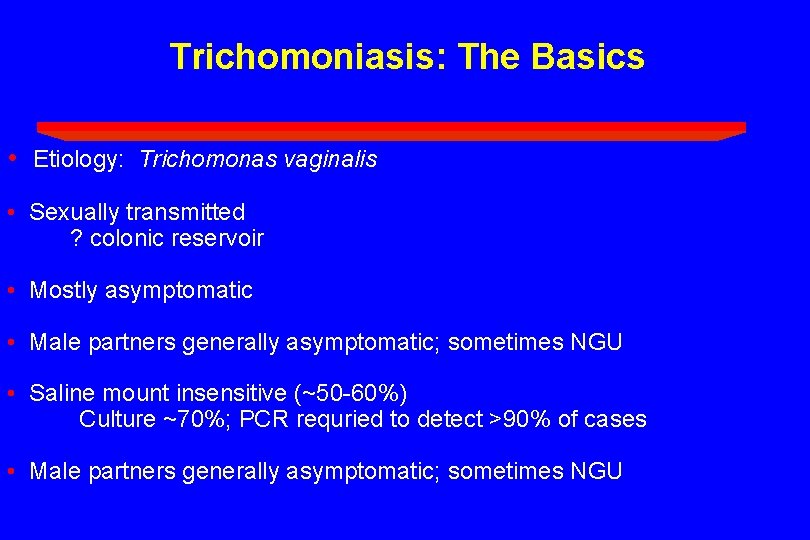

Trichomoniasis: The Basics • Etiology: Trichomonas vaginalis • Sexually transmitted ? colonic reservoir • Mostly asymptomatic • Male partners generally asymptomatic; sometimes NGU • Saline mount insensitive (~50 -60%) Culture ~70%; PCR requried to detect >90% of cases • Male partners generally asymptomatic; sometimes NGU